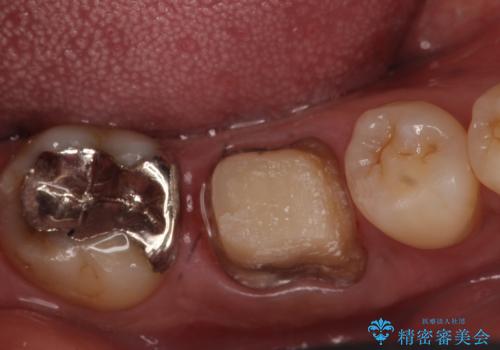

- 数か月前から右下の奥歯の歯茎から膿が出る、他院で相談したところ抜歯といわれたが何とか残せないか診て欲しいといらっしゃった方の症例です。

再根管治療を行い、フィステル(膿の出口)の消失および根尖病変の縮小を確認後、オールセラミッククラウンによる補綴を行いました。